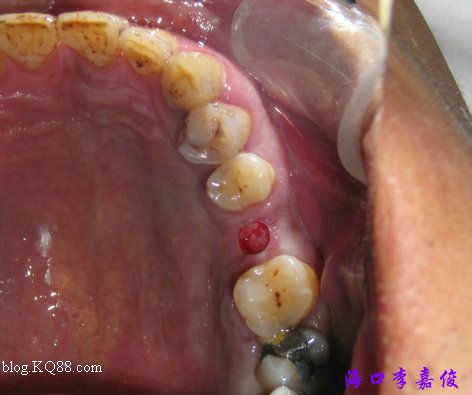

環(huán)切

牙齦厚度標準